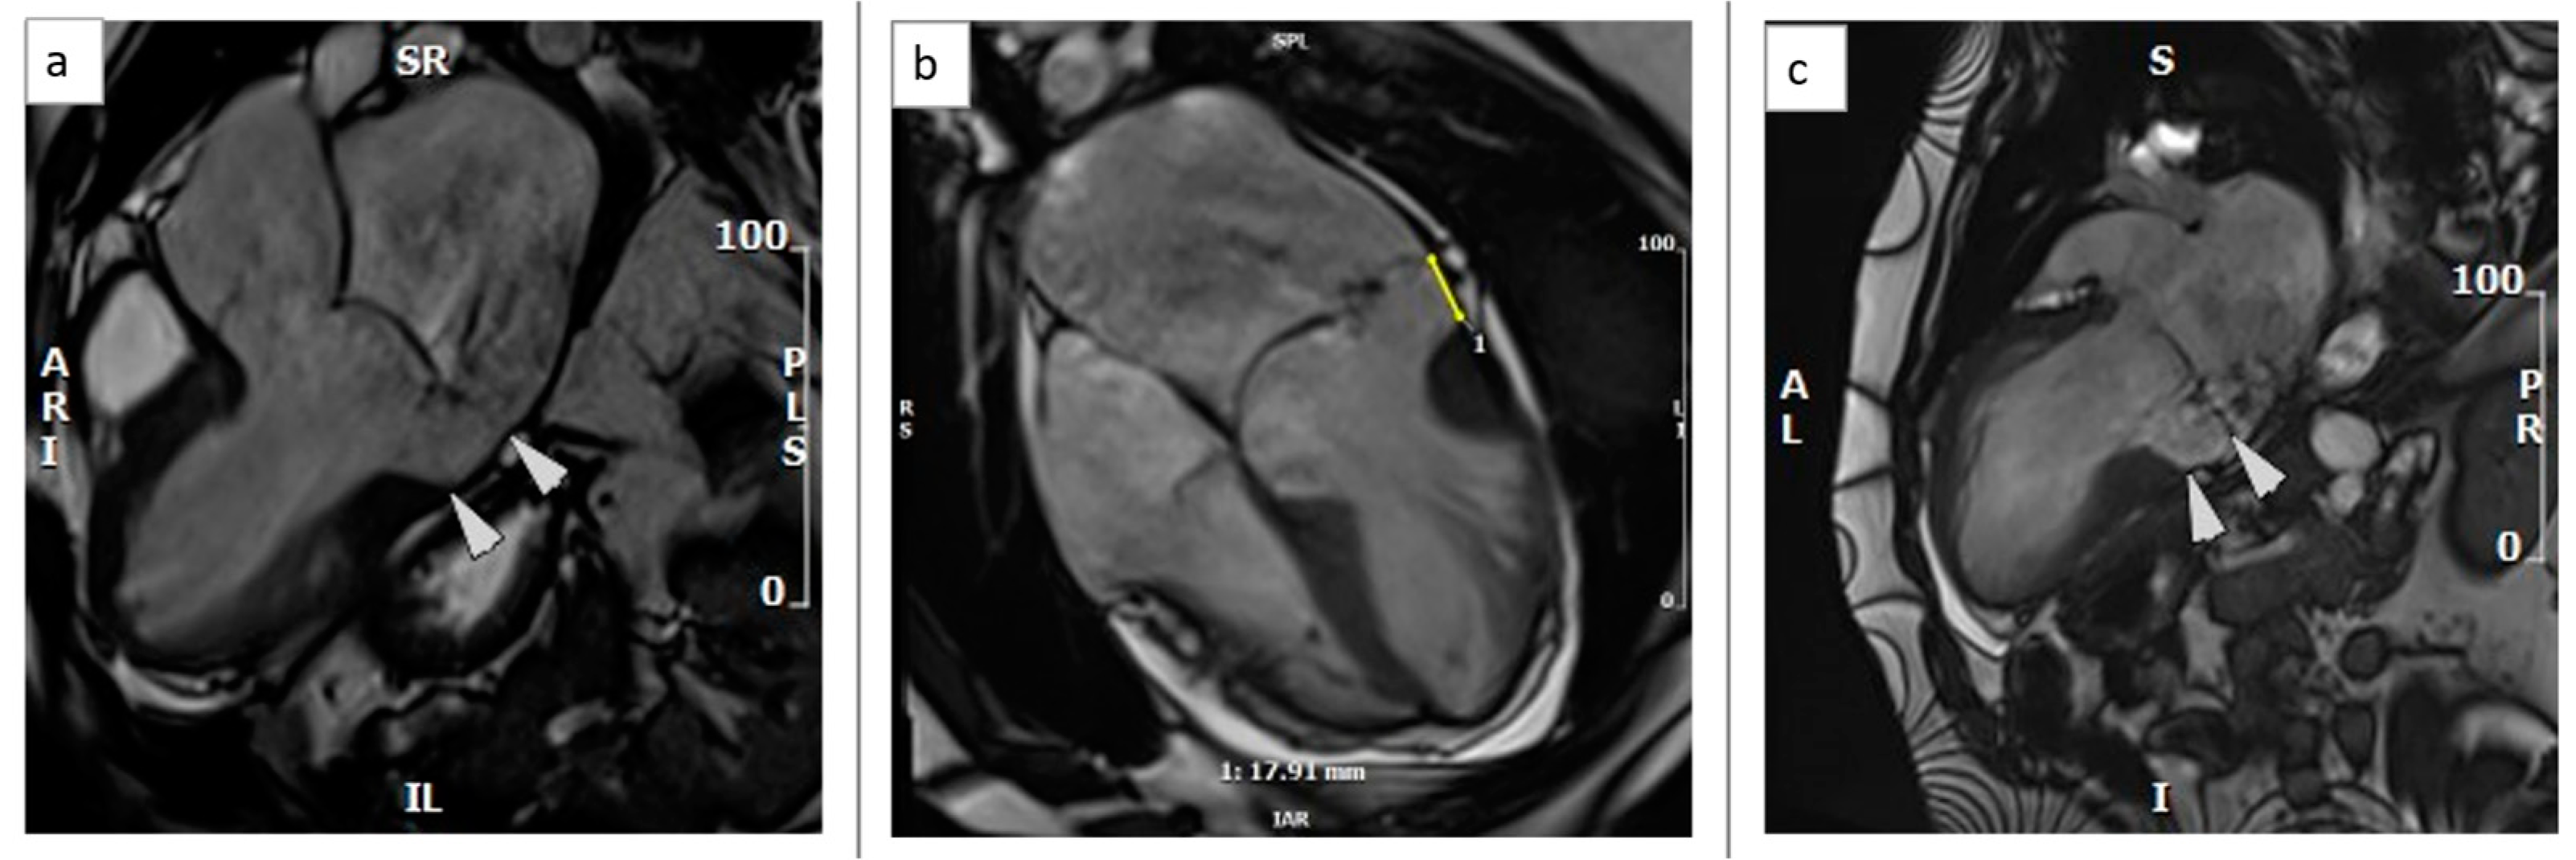

Hyper-mobility of the basal inferolateral wall with hypokinesia of the adjacent posteromedial papillary muscle indicating increased mechanical tethering of the sub-valvular apparatus was noted. As a result, there was severe holosystolic mitral valve regurgitation (regurgitant fraction 62%) into a gigantic left atrium. The left ventricle was severely dilated with an ejection fraction (EF) of 53%. In the context of severe chronic volume overload, such an EF reflected at least mild–moderate systolic function impairment (Figure 3, Video S4).

Figure 3. CMR b-SSFP still images in systole showing severe mitral valve regurgitation into a severely dilated left ventricle: (a). LVOT view, (b). HLA view, (c). VLA view.